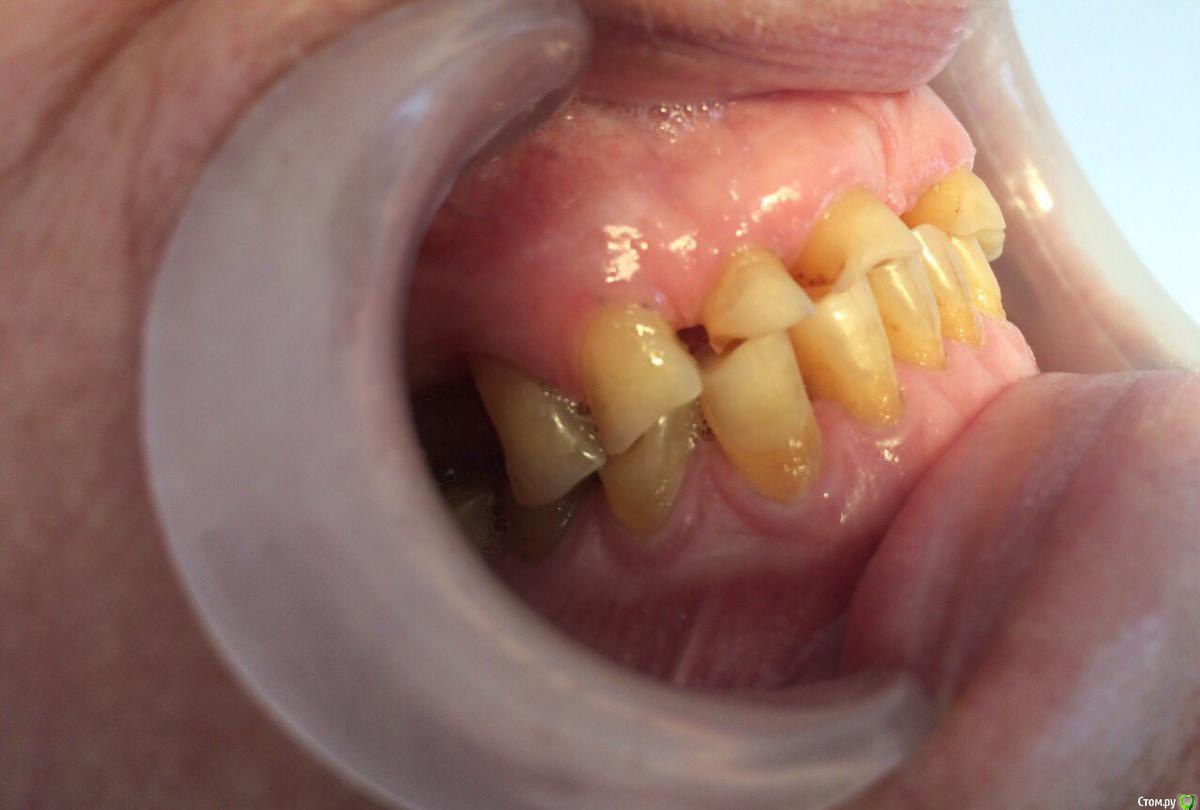

dr.Dre Опубликовано 31 июля, 2017 Поделиться Опубликовано 31 июля, 2017 Добрый вечер уважаемые коллеги ,пациентка 70 лет хочет металлокерамику,каналы очень склероризированые,как правильно протезировать при таком прикусе? Ссылка на комментарий

chervoncevdaniil Опубликовано 1 августа, 2017 Поделиться Опубликовано 1 августа, 2017 (изменено) пока пациентка хочет вверхИ что,вы хотите под такую анатомию нижних зубов ей сделать новый верх?Если хочет постоянные только верх,то на низ времянки на боковые,фронт хотя бы композитом подкорректировать,а дальше пусть хоть по зубу нижние в постоянные переводит,иначе ерунда,а не работа получится Изменено 1 августа, 2017 пользователем chervoncevdaniil 2 Ссылка на комментарий

bakagaidzin Опубликовано 1 августа, 2017 Поделиться Опубликовано 1 августа, 2017 (изменено) По уму надо делать все сразу,снять лицевую,определить ЦС,посчитать LVI и передать эти данные технику для ваксапа.а дальше уже в идеале конечно сделать мокап длительного,потом менять его на постоянные коронки..Но это все в идеале,сомневаюсь что на практике Вы это осуществите у 70 летней пациентки...плюс тут диастема огромная,нужна ортодонтия Изменено 1 августа, 2017 пользователем bakagaidzin 3 Ссылка на комментарий

Bobby Опубликовано 7 августа, 2017 Поделиться Опубликовано 7 августа, 2017 В данном случае, как правильно подметили, невозможно сделать один зубной ряд, не проводя реконструкцию антагонистов. Ссылка на комментарий